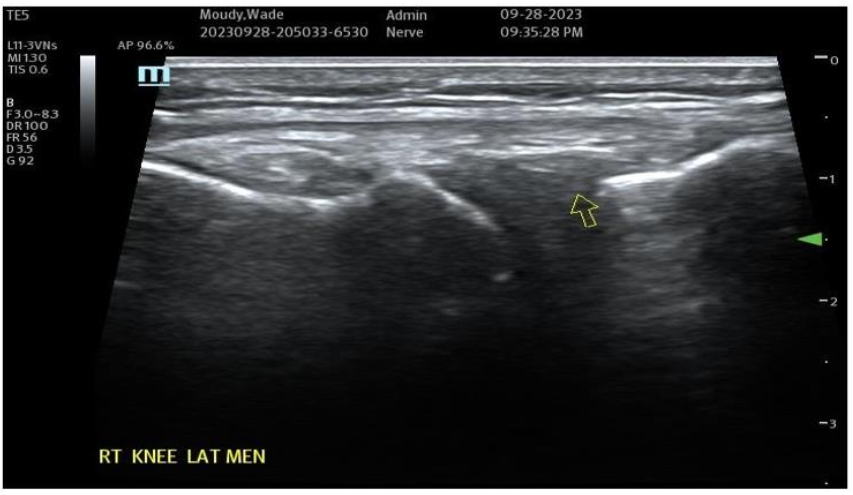

Figure 7A: Pre-Treatment Medial Meniscal/MCL Damage and Inflammatory Changes. Figure 7B: Post-Treatment with Biocellular Product (Orthobiologic) mix of Nanofat + HD PRP, this target Medial Meniscus areas (1 target of many in Knee).